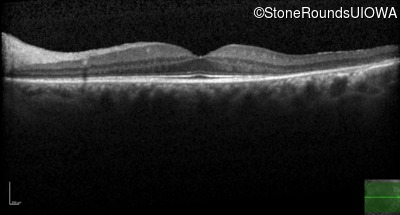

Optical Coherence Tomography - Right - 20/20

Exemplar / OCT Stack